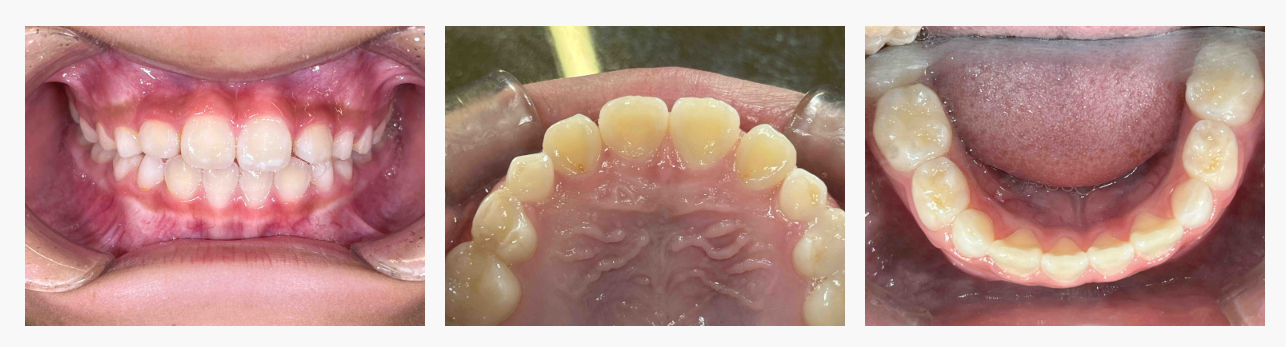

▼ Before(治療前)

初診時には、

・上下の前歯が反対に噛んでいる

・舌の位置が低く、口呼吸の傾向

・混合歯列期で、あごの成長を活かしやすい時期